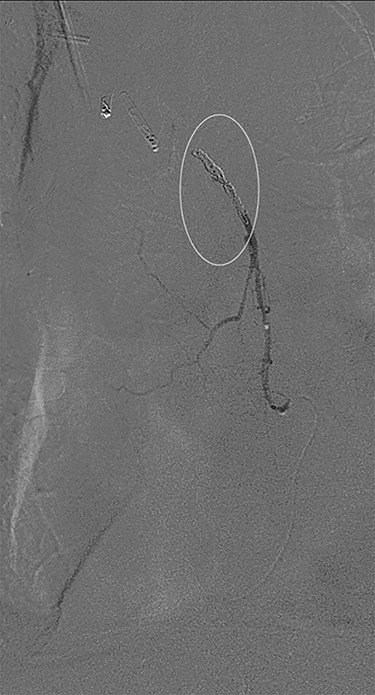

Angiography showing extravasation at the anastomosis. Curved arrow = OG anastomosis; Red arrow = contrast extravasation; Arrow MC = microcatheter.

Eight days later, he represented with an upper gastrointestinal bleed with massive haematemesis requiring immediate intubation for airway protection. Computer tomography angiography was unremarkable and an emergency gastroscopy revealed an extensive amount of blood and clot in the oesophagus and gastric conduit (limiting the view), but no active bleeding point. Conservative treatment in the Intensive Care Unit (ICU) with blood transfusion, proton pump inhibitors and life support were implemented. Another large bleed occurred 2 days later and a repeat gastroscopy revealed a non-bleeding visible vessel at the OG anastomosis and a haemostatic clip was applied. However, over the next 10 days, the patient remained blood transfusion dependent and had two further endoscopies. The first was unremarkable, but the second endoscopy re-demonstrated the luminal vessel at the OG anastomosis, with no evidence of the previously placed clip. This was felt to be the cause of his intermittent and problematic bleeding, so another haemostatic clip was attempted, resulting in pulsatile, moderate volume arterial bleeding. The procedure was abandoned and the patient transported immediately to the Interventional Radiology Suite. Right femoral access was obtained and angiography performed. The thoracic aorta was normal, so the celiac trunk was cannulated and angiography of the right gastro-epiploic artery performed (Fig. 1), revealing active extravasation of contrast at the OG anastomosis as shown in Fig. 2. A microcatheter was advanced along the length of the right gastro-epiploic artery to the OG anastomosis and coil embolization was performed (Fig. 3). Care had to be taken to ensure that the embolization was as distal as possible to limit the risk of ischaemic complications. The patient required lengthy ongoing care in the ICU for organ dysfunction but remained hemodynamically stable after embolization without evidence of conduit ischaemia. His hospital stay was obviously lengthy, but he was ultimately transferred to a rehabilitation unit.